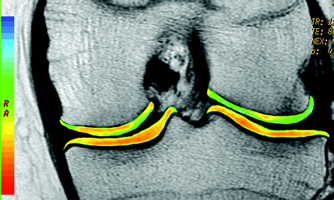

cartigram

cartigram patellofemoral 034

View from front – Knee joint